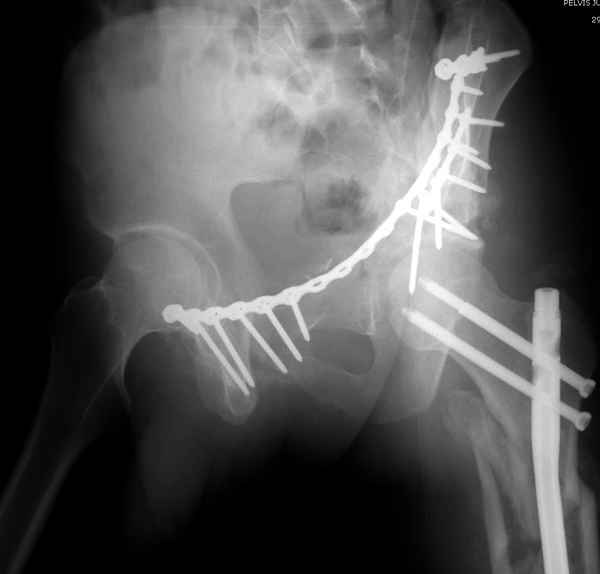

По-моему, надо готовить больного к будущей артропластике, но без опоры на задний столб невозможно удержать протез. Опорная конструкция (кольца и т.д.) должны иметь опору, и поэтому мы бы сделали реостеосинтез задним доступом. При надобности остеотомия и рутинная фиксация с межколонными винтами.

В дальнейшем, время покажет, когда приступить к артропластике....

Здесь несколько вариантов двухколонных свежих переломов, которые были оперированы из одного-заднего, а также из двух: переднего и заднего доступов.